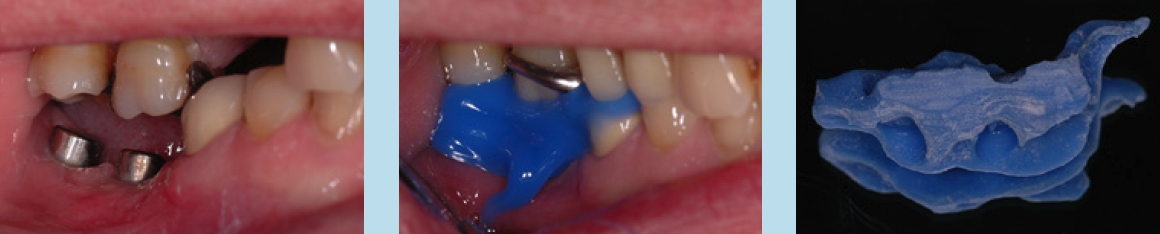

Unabhängig, ob digital oder analog vorgegangen wird, ist bei der Einbringung der Abformpfosten bzw. Scanbodies darauf zu achten, dass diese sich nicht berühren oder die Nachbarzähne touchieren. Liegen Freilegung und Implantation zeitlich weit auseinander und wurde die Lücke nicht provisorisch versorgt, kann es zum Aufwandern der Nachbarzähne kommen (Abb. 14–17). In diesem Fall ist es notwendig, die Abformpfosten zu beschleifen oder das Aufwandern kieferorthopädisch zu behandeln.

Cave: Veränderungen an den Okklusalflächen durch provisorische Füllungen oder Kronen bei fehlendem Lückenersatz können zu Zahnbewegungen in die Lücke führen. Das Tragen eines nächtlichen Retainers in Form einer Miniplastschiene kann dies verhindern.